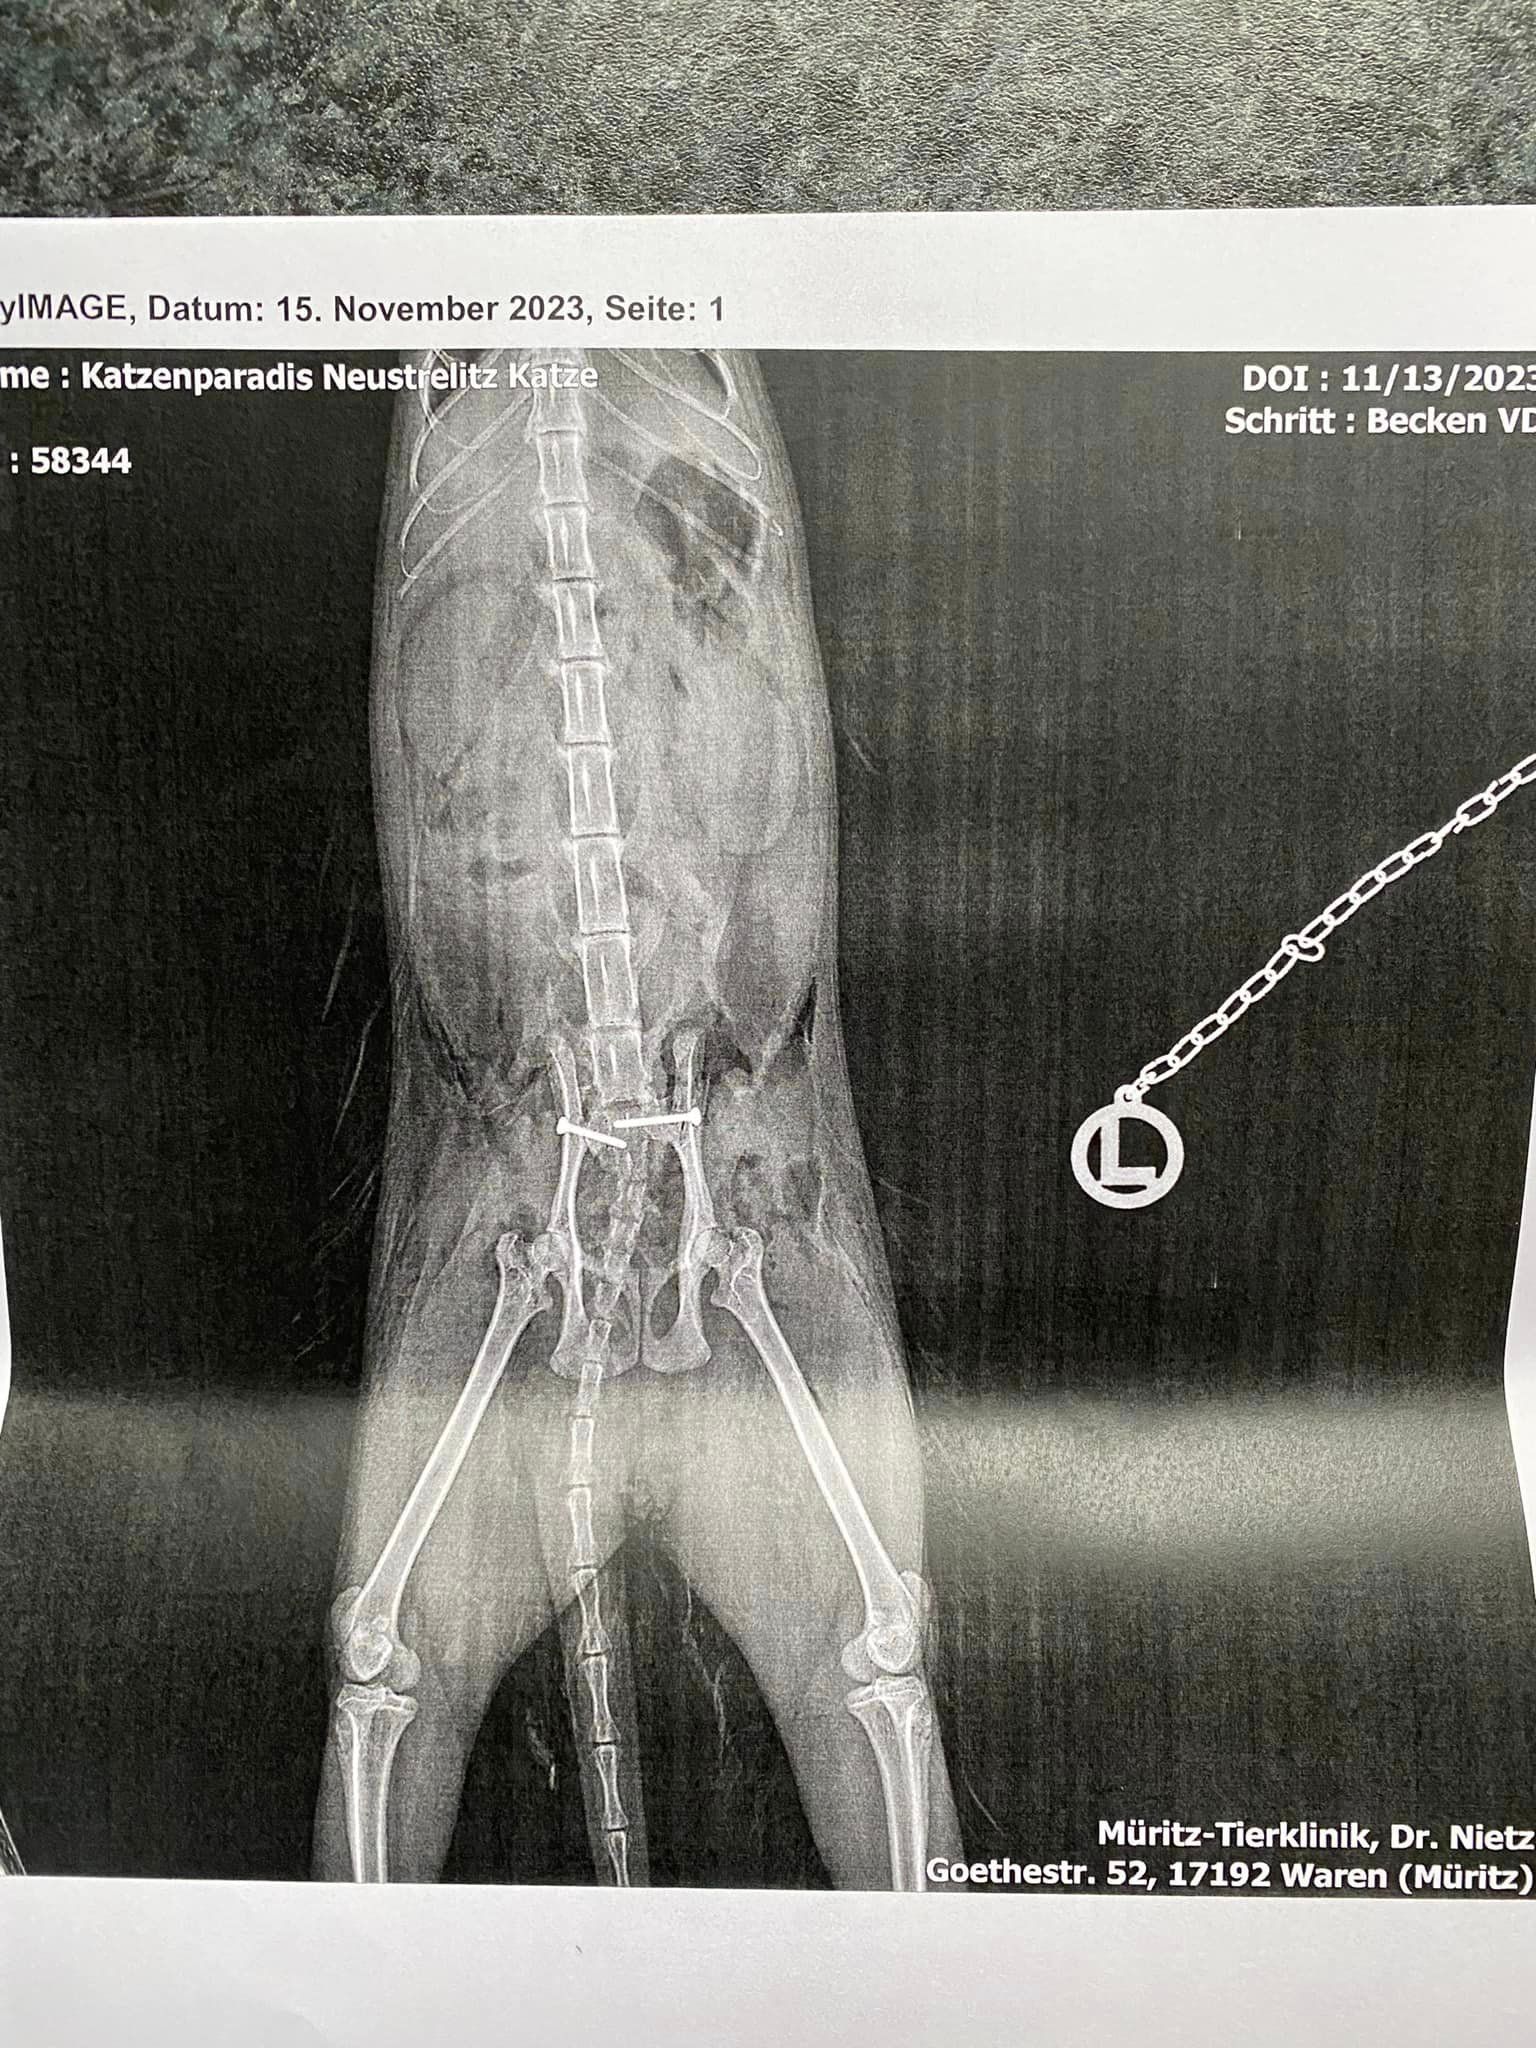

Greta hat die OP gut überstanden!

Unsere Greta hat die OP gut überstanden.

Jetzt bleibt zu hoffen, dass sie wieder lernt aufzustehen. Sie hatte zudem starke innere Blutungen und die Köpertemperatur war nicht im Normbereich.

Sie hatte wirklich Glück gefunden zu werden.

Wir belassen sie die nächsten 10 Tage noch in der Obhut der Klinik. Dort wird ihr alles zuteil, was sie benötigt inkl. Physiotherapie.